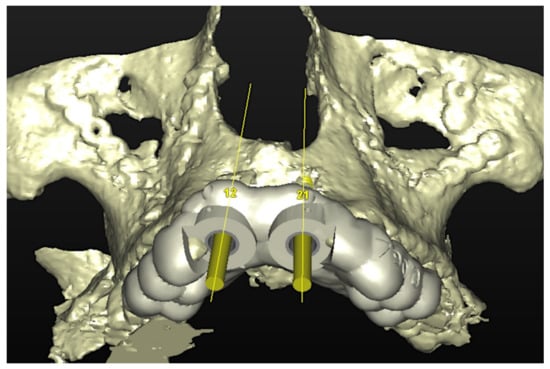

6.1.3. Image Segmentation and Virtual Planning:

The number, the length, the diameter and the placement of computational virtual implants were determined with respect to the design of the final prosthesis the available residual bone volume and the anatomical limitations according to the previously described technical procedure (Figure 3, Figure 4, Figure 5 and Figure 6).

Figure 4.

Planning of the number, the diameter, and the axis of the implant with respect to the design of the final prosthesis.